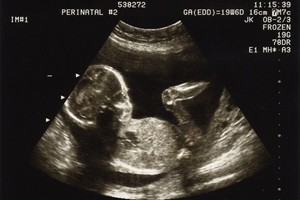

Pregnancy

Congratulations! Find reassuring pregnancy advice, shared experiences and what to expect – plus guides on what to buy. Plus, our due date calculator and brilliant baby names ideas